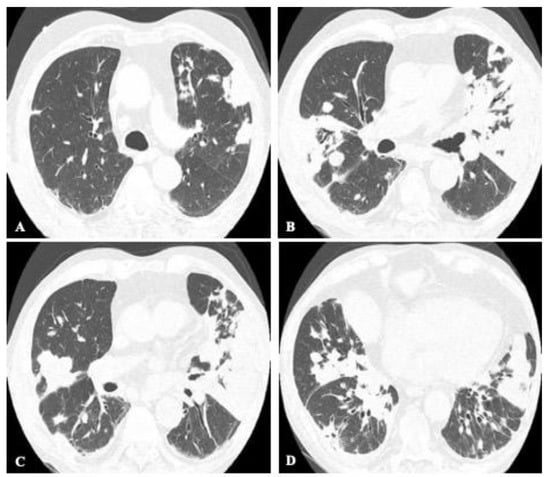

2.4. Disseminated Infection

2.5. Mixed Pattern